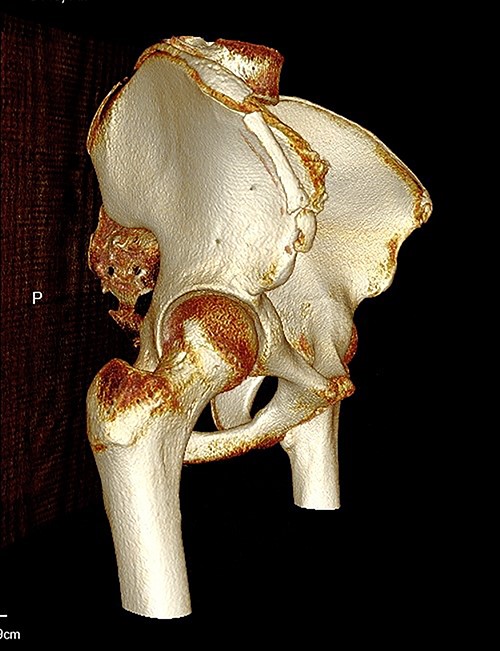

The anterior–posterior plain film X-Ray of pelvis demonstrated an avulsion fracture of the right ASIS and IC apophysis with 1.5 cm displacement (Fig. 1). Lateral view of the hip showed no extension into the joint. There was no radiological evidence of chronic overuse or previous injury. Computed tomography (CT) imaging was performed to better identify the injury; 3D volume reconstruction clearly demonstrated the unique fracture pattern of an ASIS avulsion in addition to an avulsion of the distal iliac apophysis extending ~5 cm with the described displacement (Figs 2–4).

3D reconstruction of tomographic CT scan illustrating avulsion fracture of ASIS and IC apophysis with its latero-inferior displacement (R - Right, L - Left, A - Anterior).